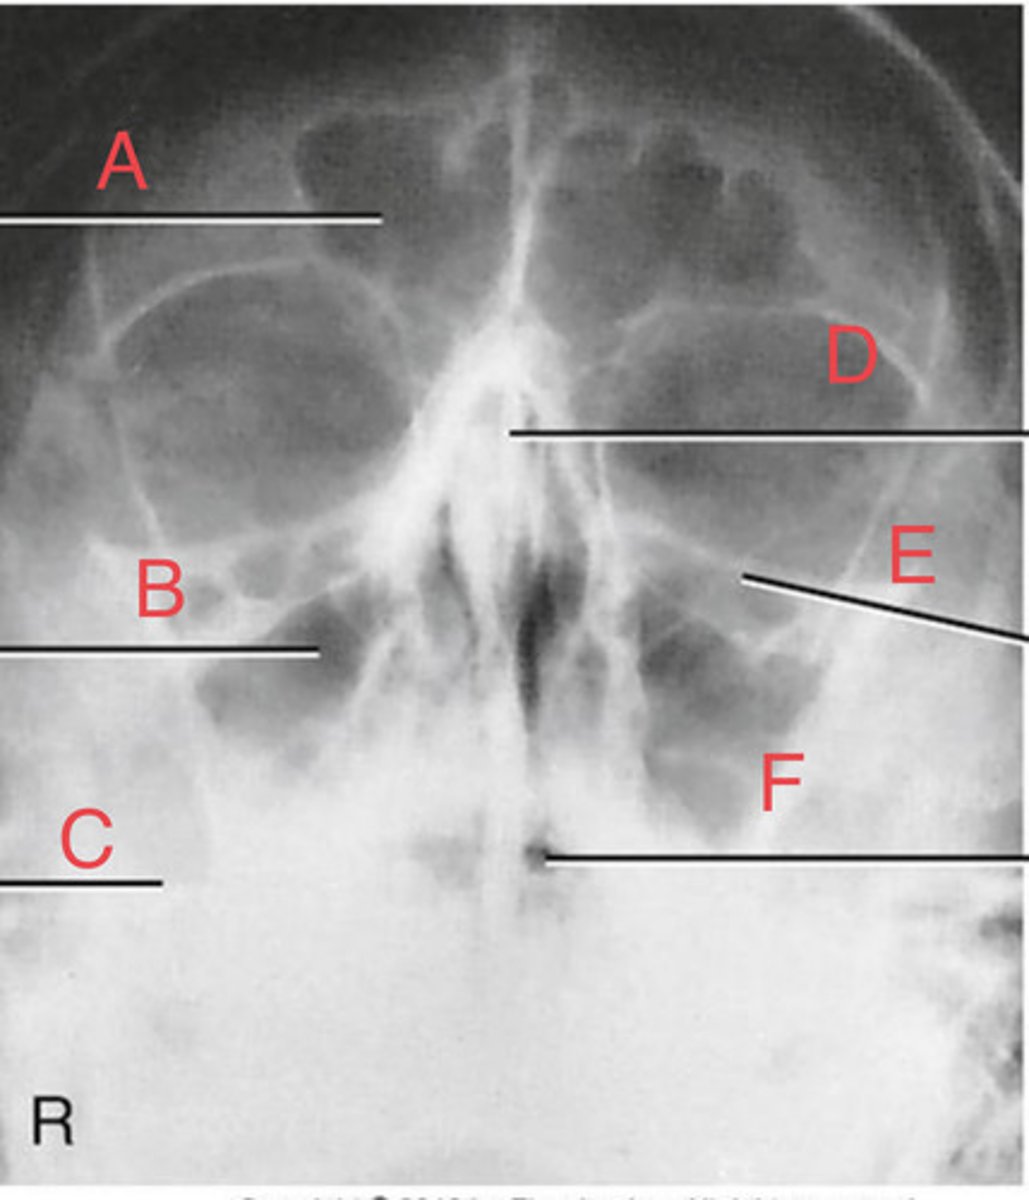

PA Caldwell Sinuses

What position?

frontal sinus of the frontal bone

A.

R. ethmoid sinus of the ethmoid bone

B.

crista galli of ethmoid bone

C.

L superior orbital fissure of the sphenoid

D.